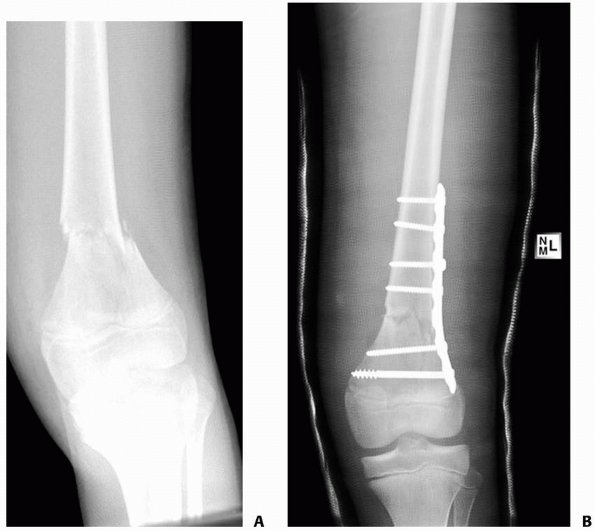

![]() |

FIGURE 22-20 AP (A) and lateral (B)

x-rays a low-energy short oblique fracture through a fibrous cortical defect in the distal femur; this type of fracture is not unusual. The surgeon judged that there was enough distance between the fracture site and the growth plate to allow external fixation. AP (C) and lateral (D) x-rays 3 weeks after external fixation shows early callus and good alignment. The external fixation was removed shortly after this x-ray and the child was placed in a long leg cast, with weight bearing as tolerated. |